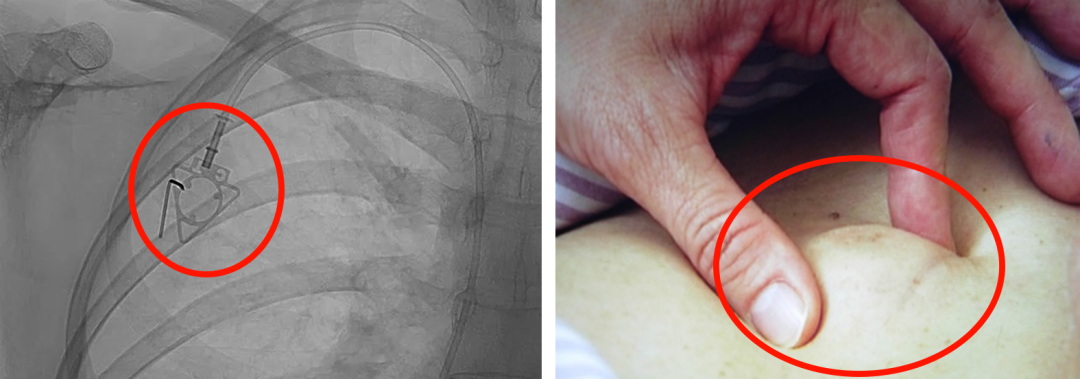

輸液港,臨床上也稱為PORT,是為了減輕藥物對患者血管刺激而置入體內(nèi)的專業(yè)輸液裝置。它分為三部分:無損傷針、置入靜脈的導(dǎo)管、埋藏在皮下與輸液針連接的注射座(港體)。注射座連接插入大靜脈的導(dǎo)管形成長期血管通路,發(fā)揮類似港口的作用,故稱作“輸液港”。